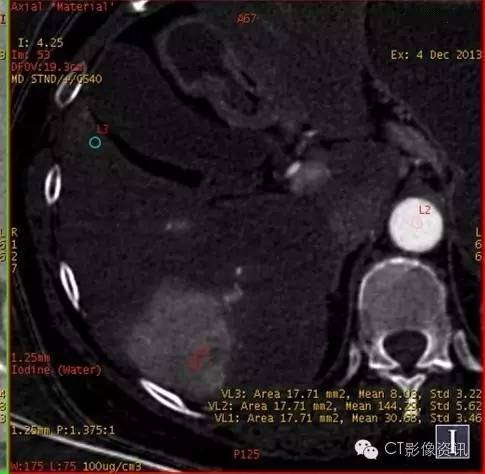

动脉期和门脉期碘基图碘含量测定

动脉期

病灶中心碘含量:30.68 主动脉碘含量:144.29 肝组织碘含量:8.03

门脉期

病灶中心碘含量:27.48 门脉碘含量:63.55 肝组织碘含量:27.10

物质分离碘(水)基像充分表现了碘密度变化的特点,不再仅局限于“快进快出”的表现,而是通过定量分析,有效避免了诸多复杂因素的影响,更加有利于原发性肝癌的定性诊断。